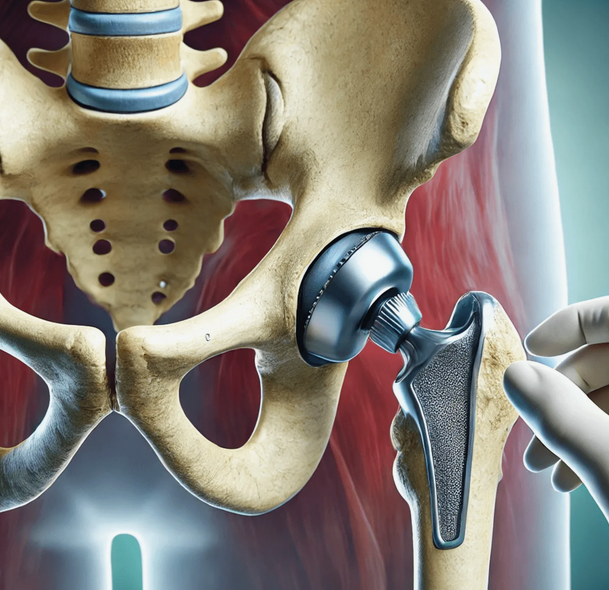

В случае перелома шейки бедра компания МосРентген Центр госпитализирует в Склиф для эндопротезирования.